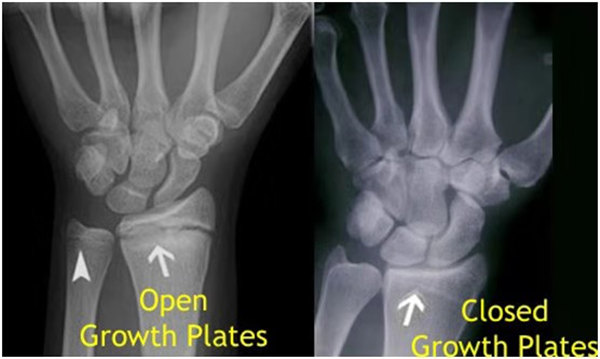

我們都知道,人體的高矮是由骨骼的生長發育決定的,特別是下肢長骨。長骨呈長管狀,在長骨的兩端有一種專管骨骼生長的骺軟骨,它與干骺端之間有一盤狀軟骨結構稱為骺板(線),在幼兒的X光片上表現為一條較寬的透光帶。 (見下圖)

未成年時隨著年齡的增加骺軟骨端不斷骨化,骨骼就不斷增長。當骨骺線完全閉合時骨骼就停止生長,個子也就不再增長了。一般骨骺端完全閉合的年齡是18~20歲左右。

其實想要了解孩子的生長發育情況或者說孩子未來身高的趨勢,測骨齡是個好辦法。臨床上通常拍攝兒童的左手正位X光片 , 采用《中華-05》骨齡標準對手腕骨發育程度進行骨齡評價。